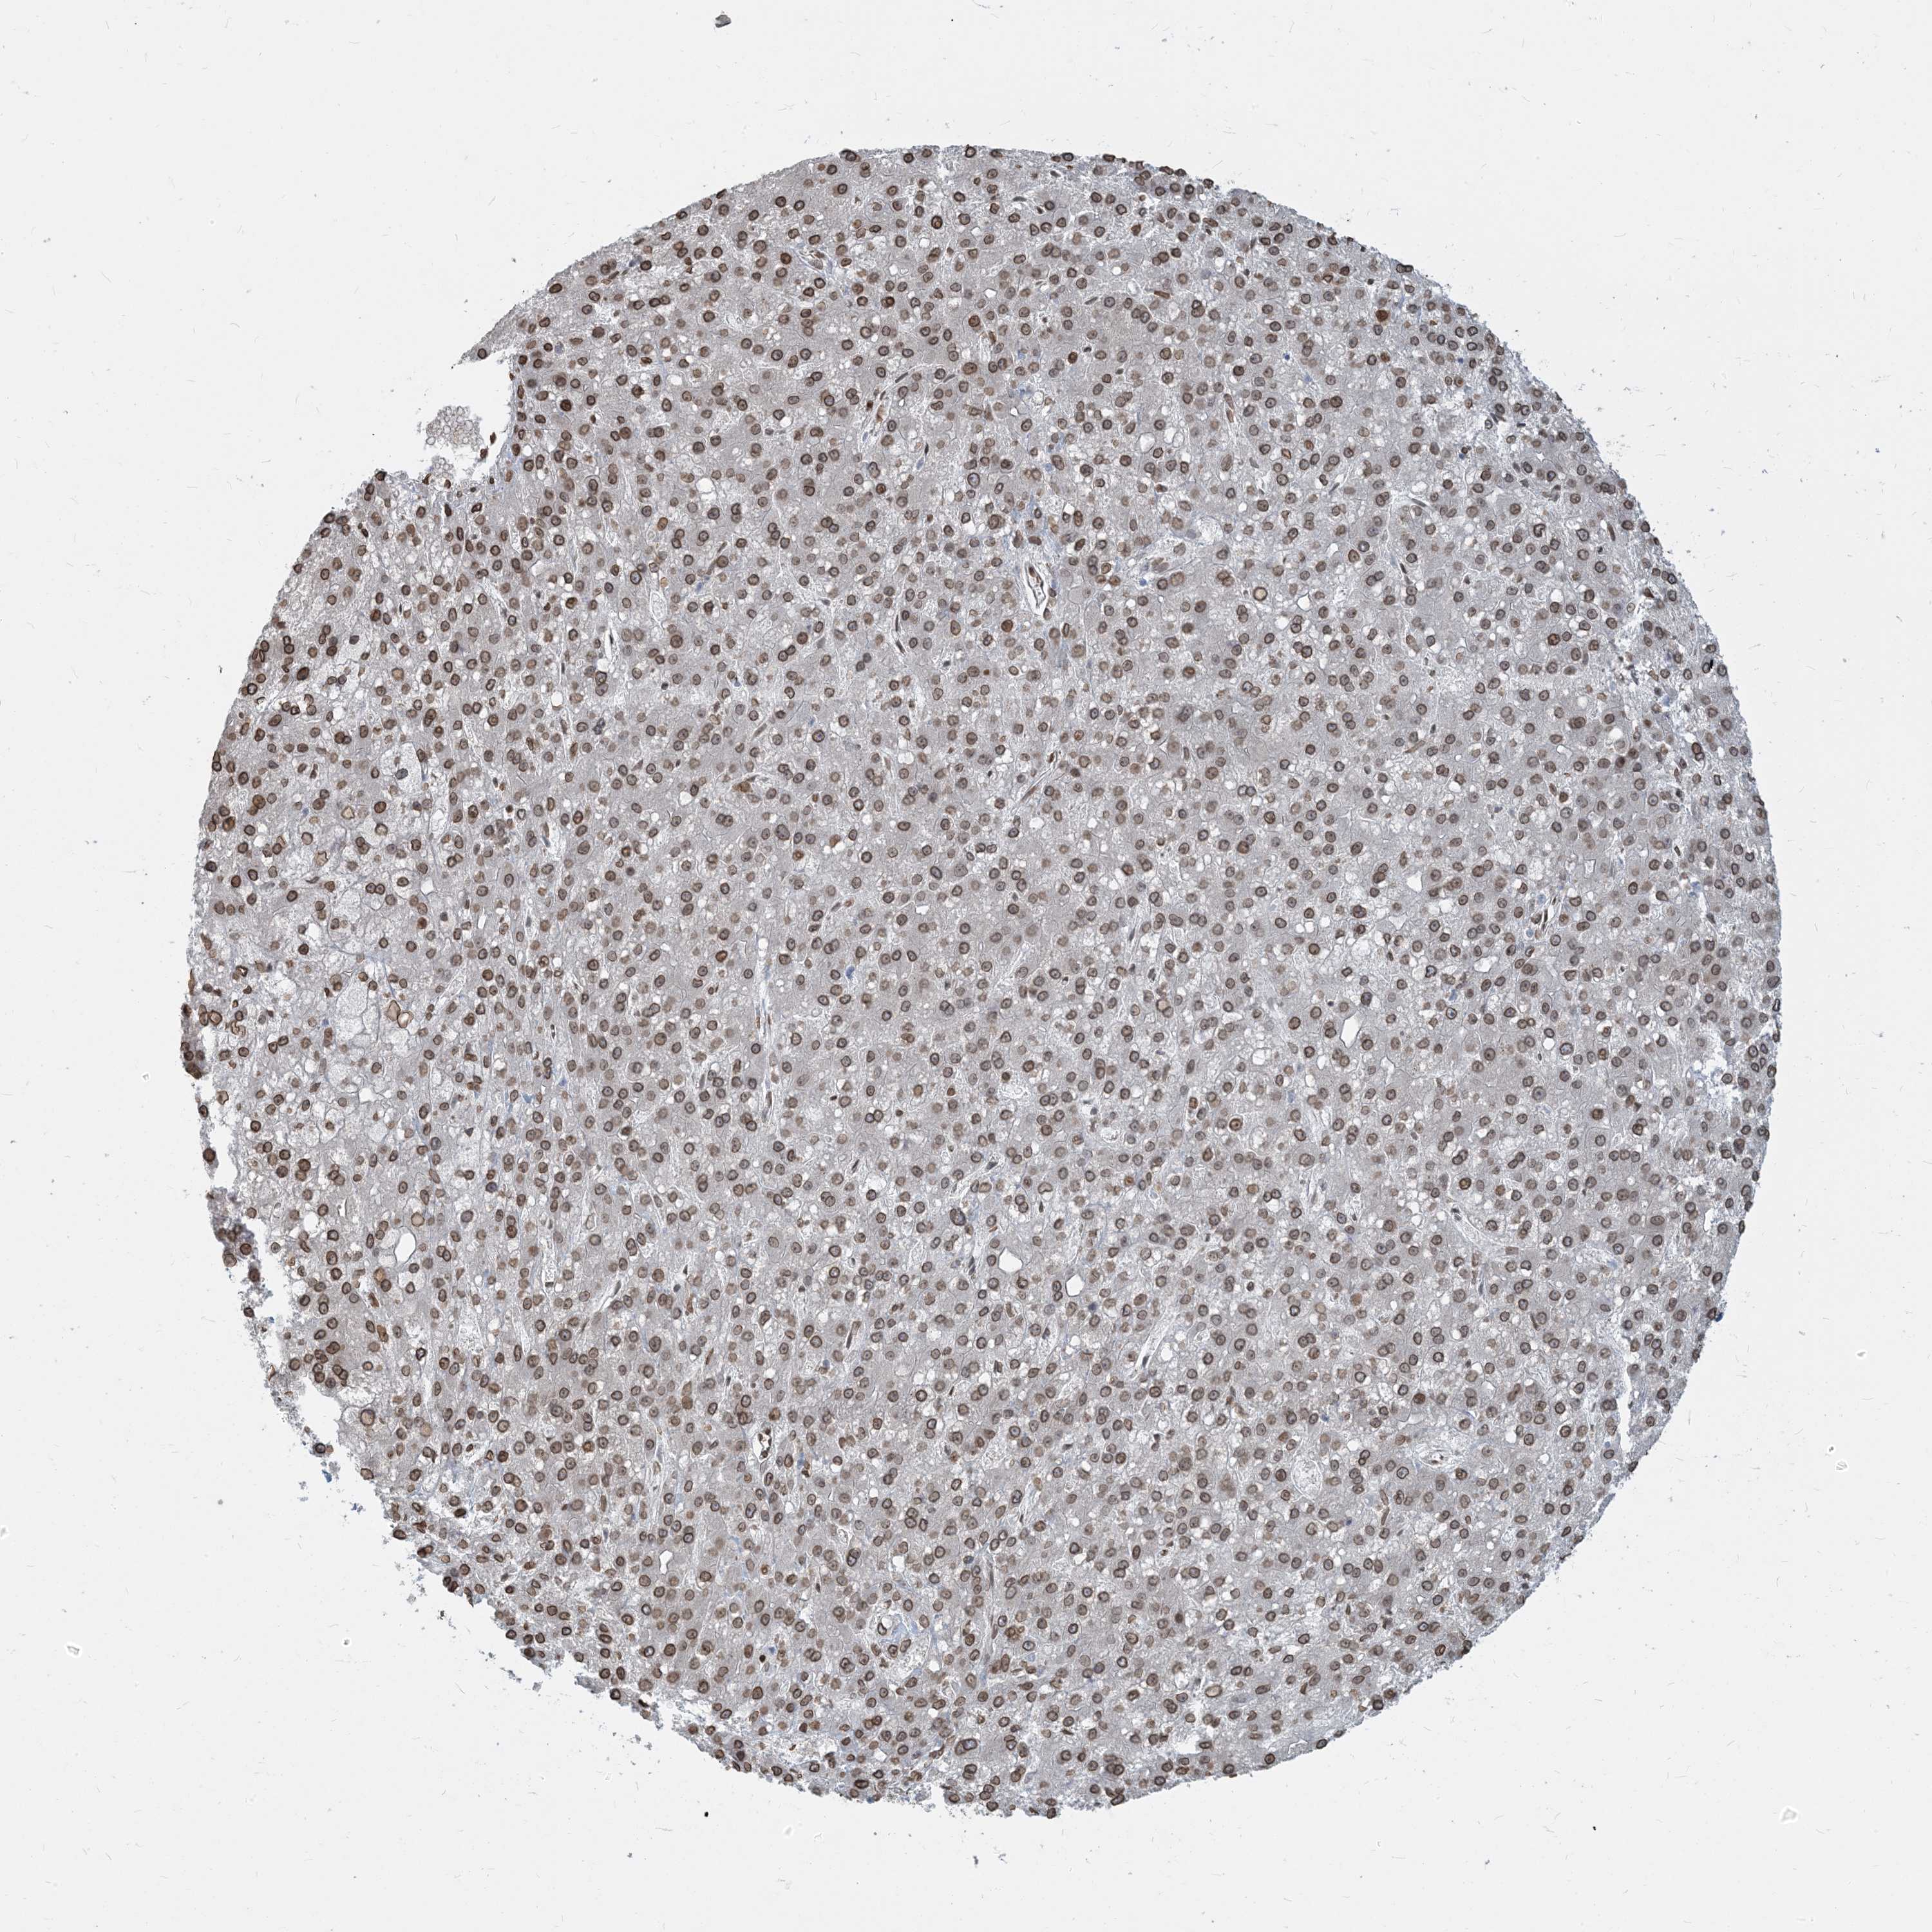

LIVER CANCER - Protein expressioni

A mouse-over function shows sample information and annotation data. Click on an image to view it in a full screen mode. Samples can be filtered based on level of antibody staining by selecting one or several of the following categories: high, medium, low and not detected. The assay and annotation is described here.

Note that samples used for immunohistochemistry by the Human Protein Atlas do not correspond to samples in the TCGA dataset.

Antibody stainingi

Antibody staining in the annotated cell types in the current human tissue is reported as not detected, low, medium, or high, based on conventional immunohistochemistry profiling in selected tissues. This score is based on the combination of the staining intensity and fraction of stained cells.

Each image is clickable and will lead to virtual microscopy that enables deeper exploration of all samples and also displays staining intensity scores, fraction scores and subcellular localization as well as patient and tissue information for each sample.

Antibody HPA023180

Staining

High

Medium

Low

Not detected

Intensity

Strong

Moderate

Weak

Negative

Quantity

>75%

75%-25%

<25%

None

Location

Nuclear

Cytoplasmic/membranous

Cytoplasmic/membranous,nuclear

Cholangiocarcinoma

Carcinoma, Hepatocellular, NOS